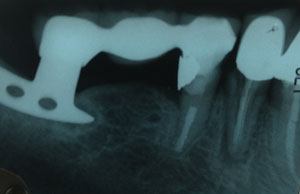

Image shows a root canal treated tooth anchoring one side of a bridge, an implant anchoring the other side

Part of the problem is that diagnosis is difficult. Typical dental x-rays can no more accurately diagnose cavitations than they can accurately diagnose subtle root canal pathology. They show only the most obvious cavitations. CT scans are excellent if all metals are absent from the mouth, but they are expensive and come with the added price tag of high radiation exposure.